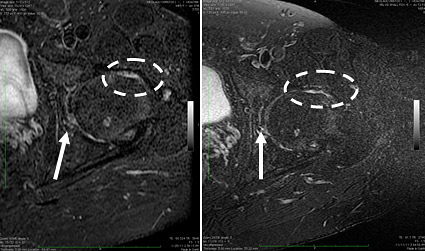

Μαγνητική τομογραφία ασθενούς πριν & 6 μήνες μετά από εμφύτευση αυτόλογων καλλιεργημένων μεσεγχυματικών κυττάρων στην άρθρωση του ισχίου για θεραπεία εκσεσημασμένης οστεοαρθρίτιδας. Με το διακεκομένο κύκλο φαίνεται η μείωση της υμενίτιδας και του οστικού οιδήματος του υποχόνδριου οστού της κεφαλής του μηριαίου, ενώ με τα βέλη φαίνεται η αύξηση του όγκου του χόνδρου στη φορτίζουσα επιφάνεια αυτής.